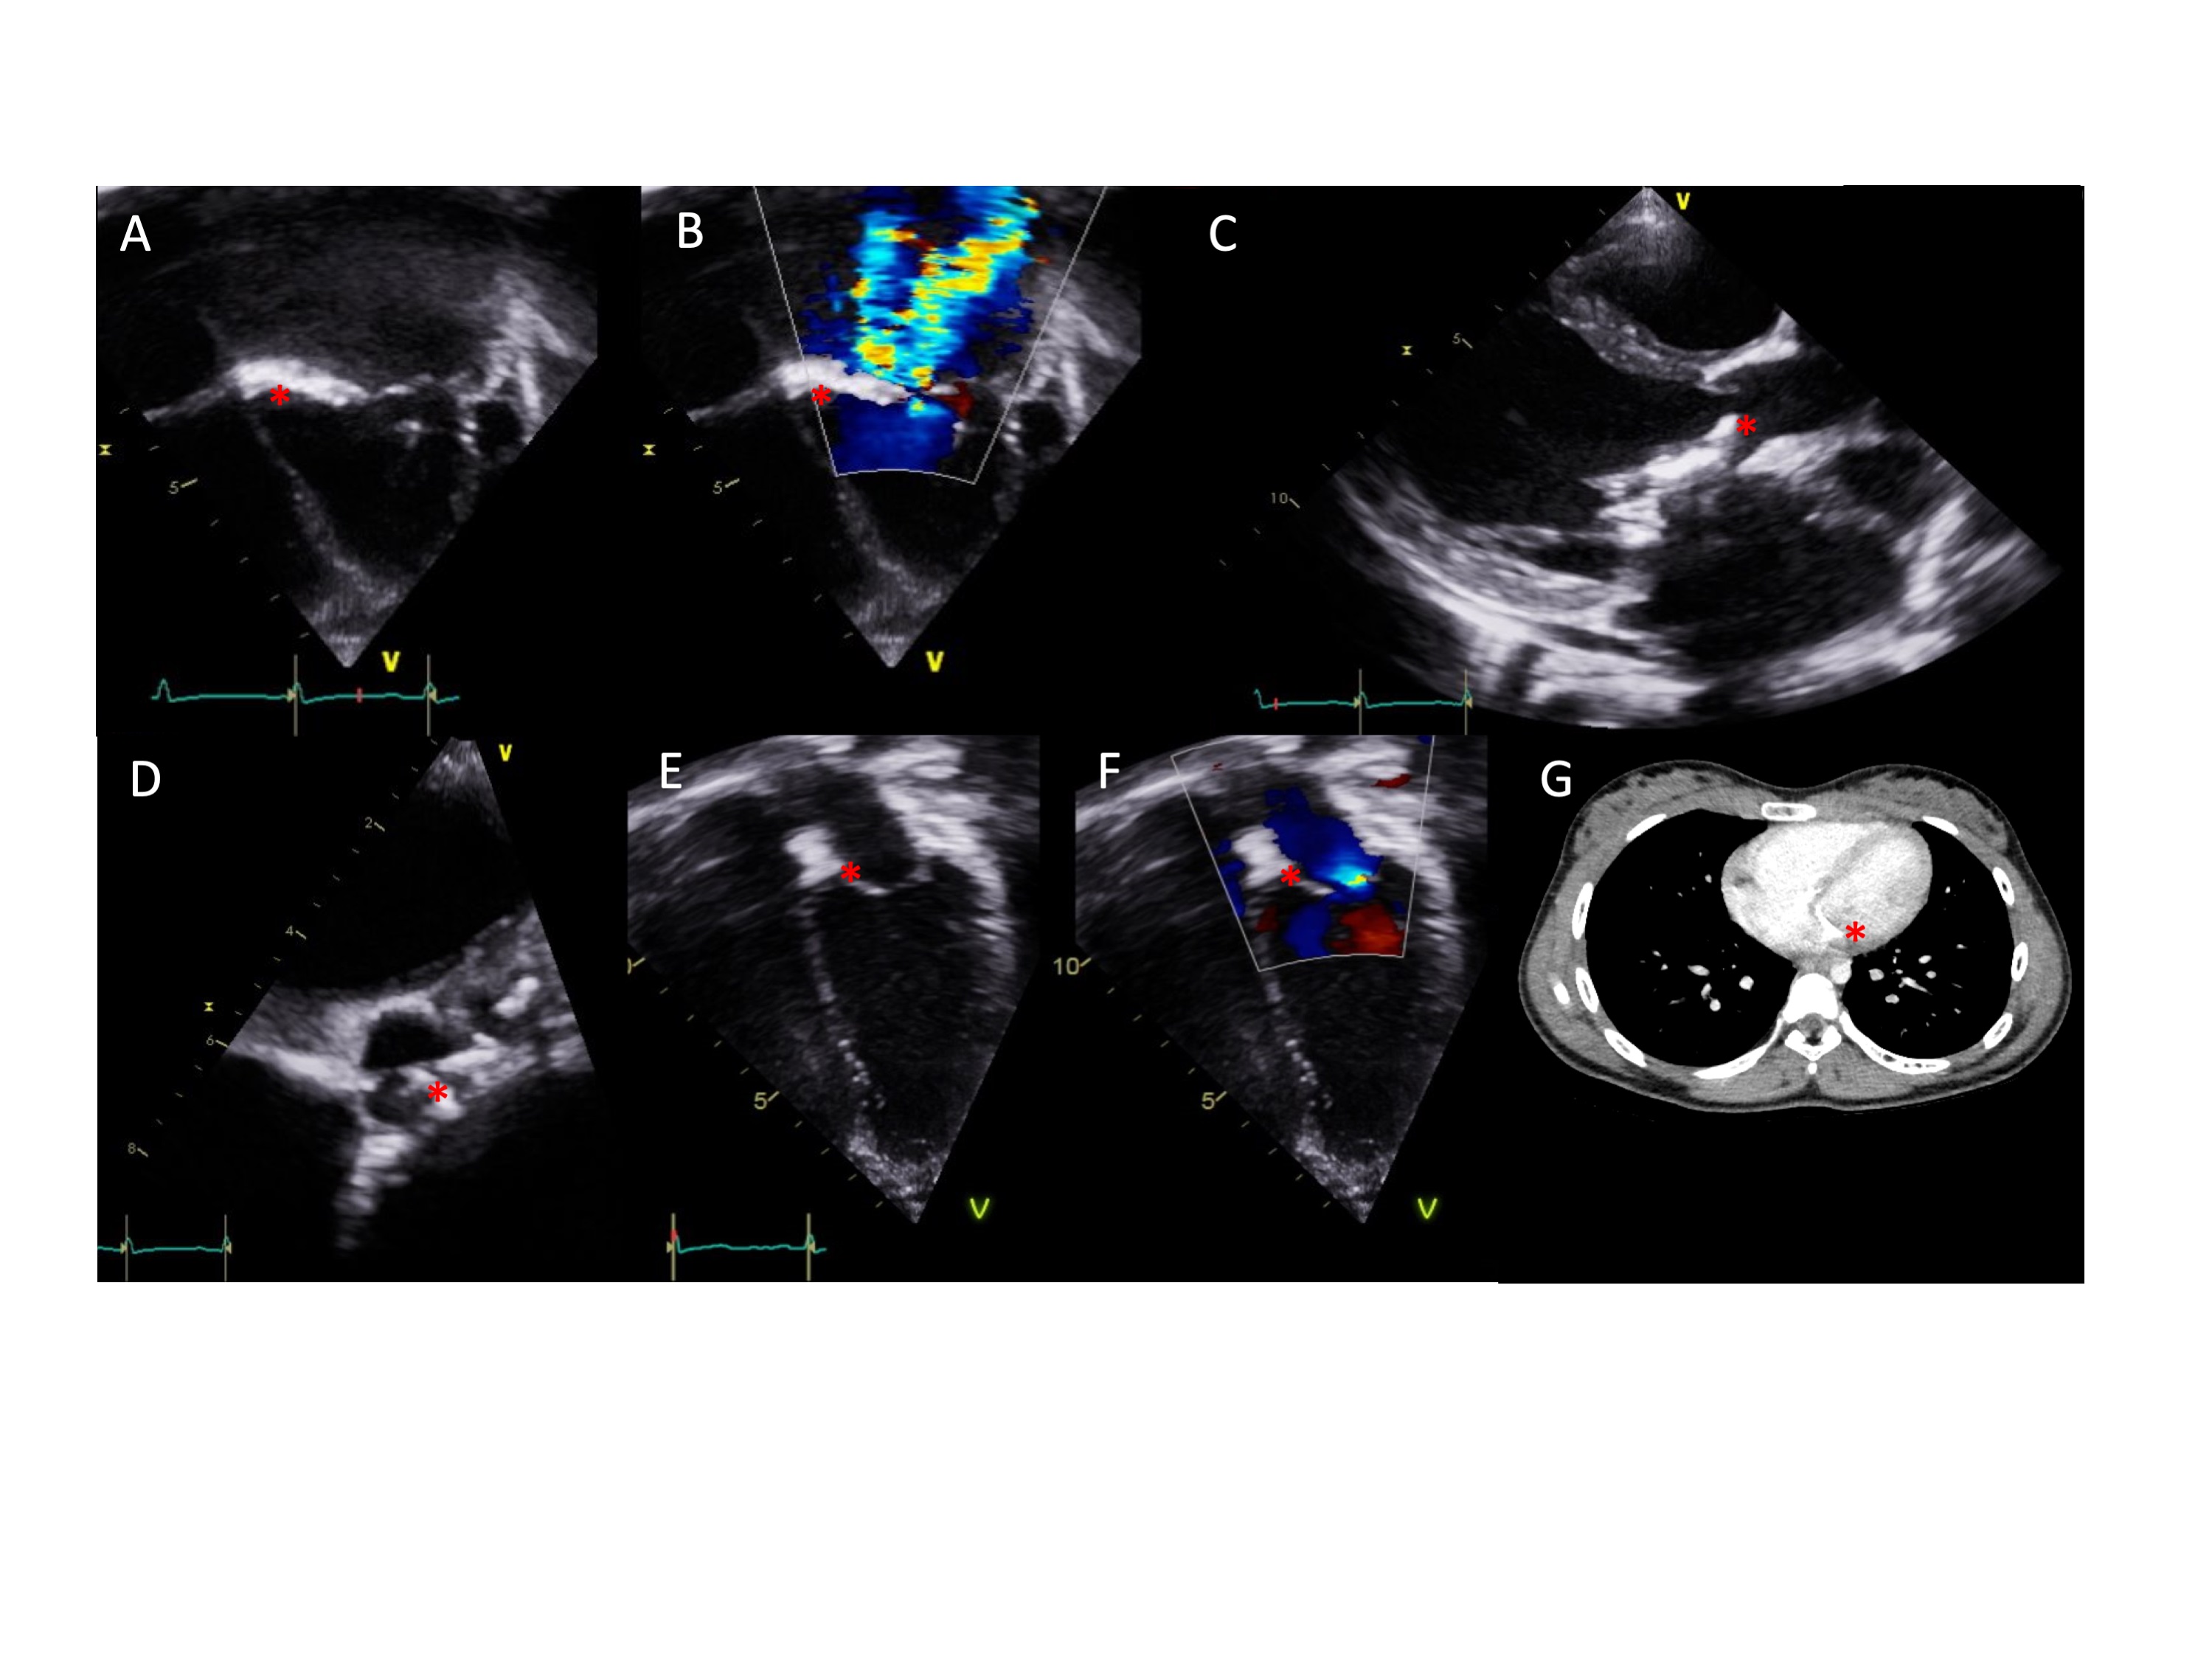

Figure 1. Echocardiogram and CT imaging. Images are annotated with a red asterisk to indicate the position of calcifications.

1A Four-chamber view demonstrating mitral valve calcification in patient 1

1B Doppler echocardiogram demonstrating severe mitral regurgitation in patient 1

1C Long axis view demonstrating aortic valve calcification in patient 1

1D Short axis view demonstrating calcification of non-coronary and left coronary cusps of the aortic valve in patient 1

1E Four-chamber view demonstrating mitral valve calcification in patient 2

1F Doppler echocardiogram demonstrating mild mitral regurgitation in patient 2

1G Computed tomography (CT) imaging demonstrating mitral valve calcification in patient 3